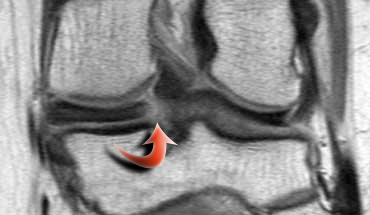

Hãy quan sát hình ảnh bên trái và cố gắng xác định vấn đề của sụn chêm này là gì.

Như bạn đã đoán được qua tiêu đề của đoạn này, đây là một trường hợp sụn chêm lật (flipped meniscus).

Sụn chêm lật là một dạng đặc biệt của rách dạng quai xô (bucket-handle tear).

Sụn chêm lật xảy ra khi mảnh vỡ của sừng sau bị lật ra phía trước, khiến sừng trước của sụn chêm có vẻ to hơn bình thường.

- Sừng sau quá nhỏ và sừng trước có vẻ to hơn với đường viền không đều.

- Thoạt nhìn có vẻ như có một đường rách dọc ở sừng trước, nhưng thực chất phần sau của cấu trúc này chính là phần lật của sừng sau bị rách.

Cấu trúc phía trước là sừng trước.

Cũng cần lưu ý tình trạng phù tủy xương khu trú và dấu ấn lõm sụn khớp. - Cấu trúc phía trước là sừng trước.